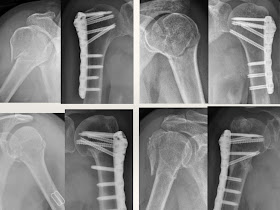

最近被邀請到韓國trauma update以及國內第一屆Pan-Asia Orthopedic Trauma Symposium演講這個題目,想一想還是寫個網誌做個小筆記好了。

約兩年前,美商捷邁公司(Zimmer)推出一項plate產品,叫NCB-PH系統

這是截至目前為止市面上唯一一種可以用對準工具(jig)做微創手術的產品

我便從那時開始使用,直到現在,共累積了15個病例。

對於two part fracture,也就是比較不那麼碎的近端肱骨骨折,

我個人認為這大概是最好的選擇了!

傷口小、恢復快、併發症較少、減少軟組織破壞.....等等優點

在我的經驗中,手術後的恢復速度比之前用一般的互鎖式鋼板(locking plate)略快

但是比傳統鋼板、也就是健保給付的鋼板,好上非常多

我也很幸運的,所有病例中沒有遭遇到嚴重的併發症,

如:感染、螺釘鬆脫、缺血性壞死等等,而需要再開一次刀做處理.....等